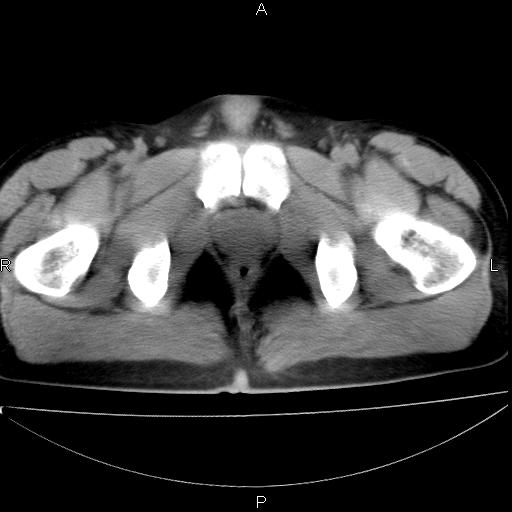

男 25岁 自述 尿频尿急,排尿困难20多天.无腰痛, b超说左肾盂轻度积水,左输尿管上端扩张.未见结石影. ct我看双侧肾盂轻度积水,双输尿管上端都扩张,大家看看能看见结石吗?

双肾轻度积水,双侧输尿管上段扩张(原因待查)。

双输尿管扩张下端未见高密度结石和输尿管晕轮征,不好说是结石.增强后如何?

双肾轻度积水,未见明确结石,薄层对结石检出率较高。

双侧输尿管上端扩张,未见明确结石,可进一步ivp检查。

考虑肾外肾盂 前列腺轻度肿大 密度欠均 考虑炎性改变

双肾盂及双输尿上段轻度积水,双输尿管未见明显结石影。